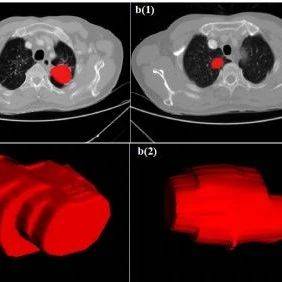

在18F-FDG PET/CT影像检查中,通过追踪FDG(一种不可代谢的葡萄糖衍生物,癌细胞“嗜”糖),可以检测并对肿瘤进行分期,临床医生能够量化癌细胞带来的糖酵解增加。其中,标准摄取值(SUV)是诊断中广泛应用的一种简单的半定量指标,但该指标的结果容易受到很多因素的影响,包括摄取动力学、体重指数或注射显影剂后的时间等。在所有动力学模型中,更为定量的Patlak分析通常被视为黄金标准,需要通过在目标组织上动态采集信息,计算摄取速率常数Ki(即18F-FDG净流入速率常数)。

对于原发肿瘤,M1组的SUV及Ki均高于M0组;

对于纵隔转移淋巴结,M1组与M0组的SUV无统计学差异,而M1组的Ki显著高于M0组。

同时研究者观察到,部分SUV相似的淋巴结,Ki却有着明显差异,这种差异与病理证实提示淋巴结的良恶性的结果高度一致。

因此,研究者认为,Ki可能成为早期无创鉴别NSCLC患者纵隔转移淋巴结的重要工具,其检出NSCLC恶性转移淋巴灶的能力比常规SUV更加灵敏。